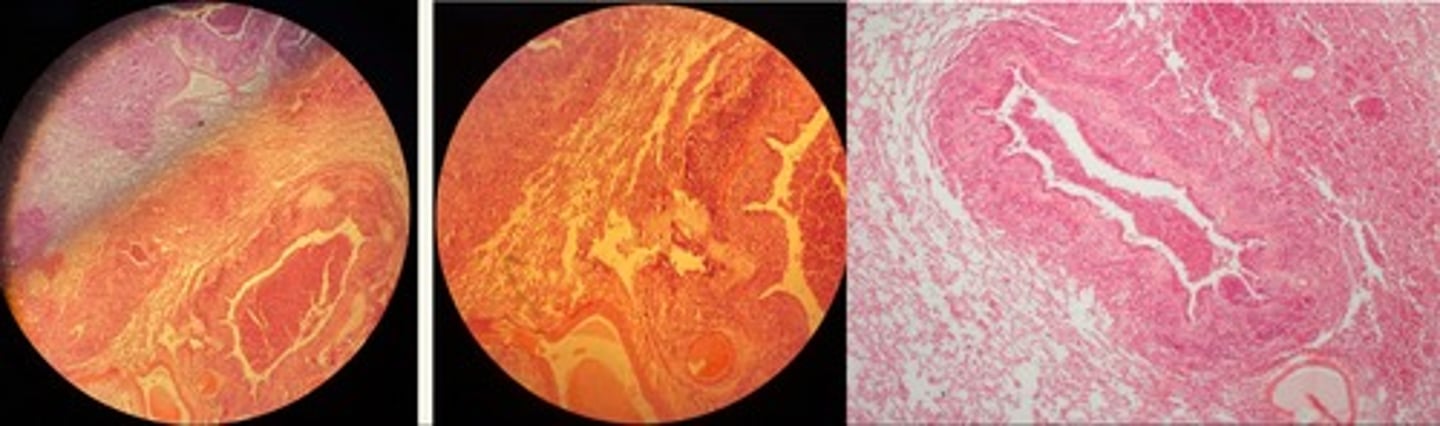

Fibrinous Bronchopneumonia => mosaic appearance

· Acute = capillaries congested + alveoli filled w/light pink fluid

· Red = alveoli filled w/ exudate = fibrin + RBCs

· Grey = lots of neutrophils in lumen

· Resolution = fibrin in strands due to neutrophils enz release